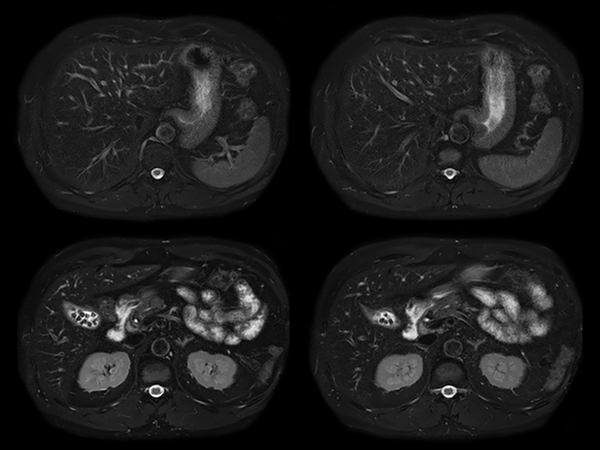

Total Torso imaging - MultiVane XD